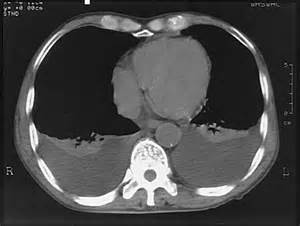

KT – plevral xəstəlikləri dəqiqləşdirən müayinədir.

Plevrada mayeni rentgen göstərə bilər. Qabırğa-diafraqma cibinin düzləşməsi, plevrada homogen kölgəlik, Damuaze xətti mayenin rentgenoloji əlamətləridir. Qabırğa-diafraqma xəttinin düzləşməsi plevrada ən azı 250 ml mayenin olduğunu göstərir. Lakin, mayeni görmək üçün ən həssas müayinə USM-dir.

Plevral mayenin biokimyəvi (protein, albumin, qlükoza, LDH, pH), mikrobioloji (qram boyama, kültür) və sitoloji müayinələri əksər hallarda mənşəyi və xarakteri barədə yetərli məlumat verə bilir. Klassik olaraq plevral maye transudat və eksudat olaraq iki yerə bölünür. Ürək, qaraciyər və böyrək yetməzliklərində adətən transudativ xarakterlı mayelər olur. Eksudativ maye isə adətən iltihabi və bədxassəli xəstəliklərdə daha çox rast gəlir. Bu xəstəliklərin müəyyənləşdirilməsində isə KT faydalıdır.

Ağciyərin periferik törəmələri, döş qəfəsi divarının, divar aralığının, diafraqmanın, diafraqmaaltı orqanların törəmələri rentgendə və USM-də plevra proyeksiyasında görünə bilər. USM periferik kütlələrin xarakterini, plevral dəyişiklikləri göstərə bilir, lakin bunun hansı orqana mənsub olduğunu dəqiqləşdirmək üçün adətən KT lazım gəlir.